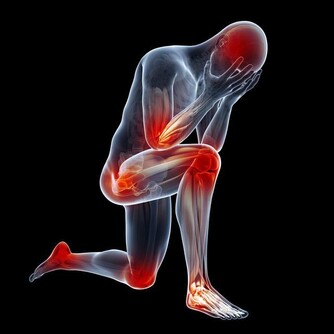

關節僵硬:它們最怕5個字

關節是骨骼之間的連接點,一旦關節出了問題,人的行動力就會受限,久之人就垮了。

關節不好的患者,對心血管系統、呼吸系統、骨骼肌系統等會造成一定影響。

因關節病長期臥床的老年人,也會引發骨質疏鬆、褥瘡、消化系統疾病。

關節在生活中最怕幾個字:

1、怕老:隨著年齡的增長,人體軟骨營養缺乏,骨骼中的無機物增多,骨骼彈力與韌性減低,易導致關節軟骨和骨退行性病變。

2、怕胖:體重增加,下肢關節承重的壓力也會增加,引起體位、步態變化,改變關節的生物力學,發生膝內翻或膝外翻,也就是常說的“O”形腿或“X”形腿。

3、怕傷:在運動、出行的過程中,如果出現急性外傷,一定要及時去醫院治療,以免留下後遺症。

不及時治療或充分休息,容易留下病根,比如“習慣性崴腳”。

4、怕勤:關節用得太狠,容易導致機械磨損,破壞軟骨。

頻繁爬山、爬樓等是非常傷害關節的。建議大家平時通過慢跑、游泳鍛煉,既不損傷關節又能鍛煉。

5、怕冷:關節受涼會引起疼痛,易導致關節僵硬。